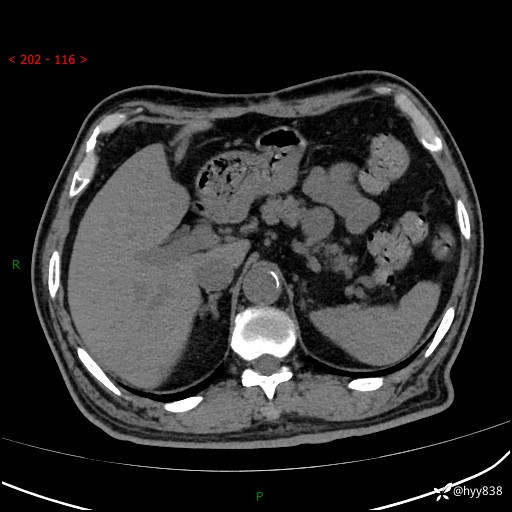

69岁/男,四肢无力3月余。胰腺囊实性占位,渐进性强化---结果公布~

【患者信息】:69岁/男

【主诉】:四肢无力3月余。

【现病史及既往史】:患者3月前无明显诱因出现四肢乏力,伴有口干、多饮、多尿等症状,无畏寒、发热、恶心、腹痛、腹泻等其他症状,于2024-06-13来我院住院治疗,完善相关辅助检查后,考虑“2型糖尿病”,予以降糖(阿卡波糖片 50mg po tid、德谷门冬双胰岛素注射液 8iu 早餐前 皮下注射)等治疗,口干、多饮、多尿较前缓解,血糖控制可;现仍存在四肢乏力,于2024-08-28来我院门诊就诊,查血钾2.88 mmol/L ,现以“低钾血症”收入我科。 本次起病以来,患者精神、饮食、睡眠良好,二便正常,近3月余体重下降约5kg。

【检查】:胰腺CT平扫+增强